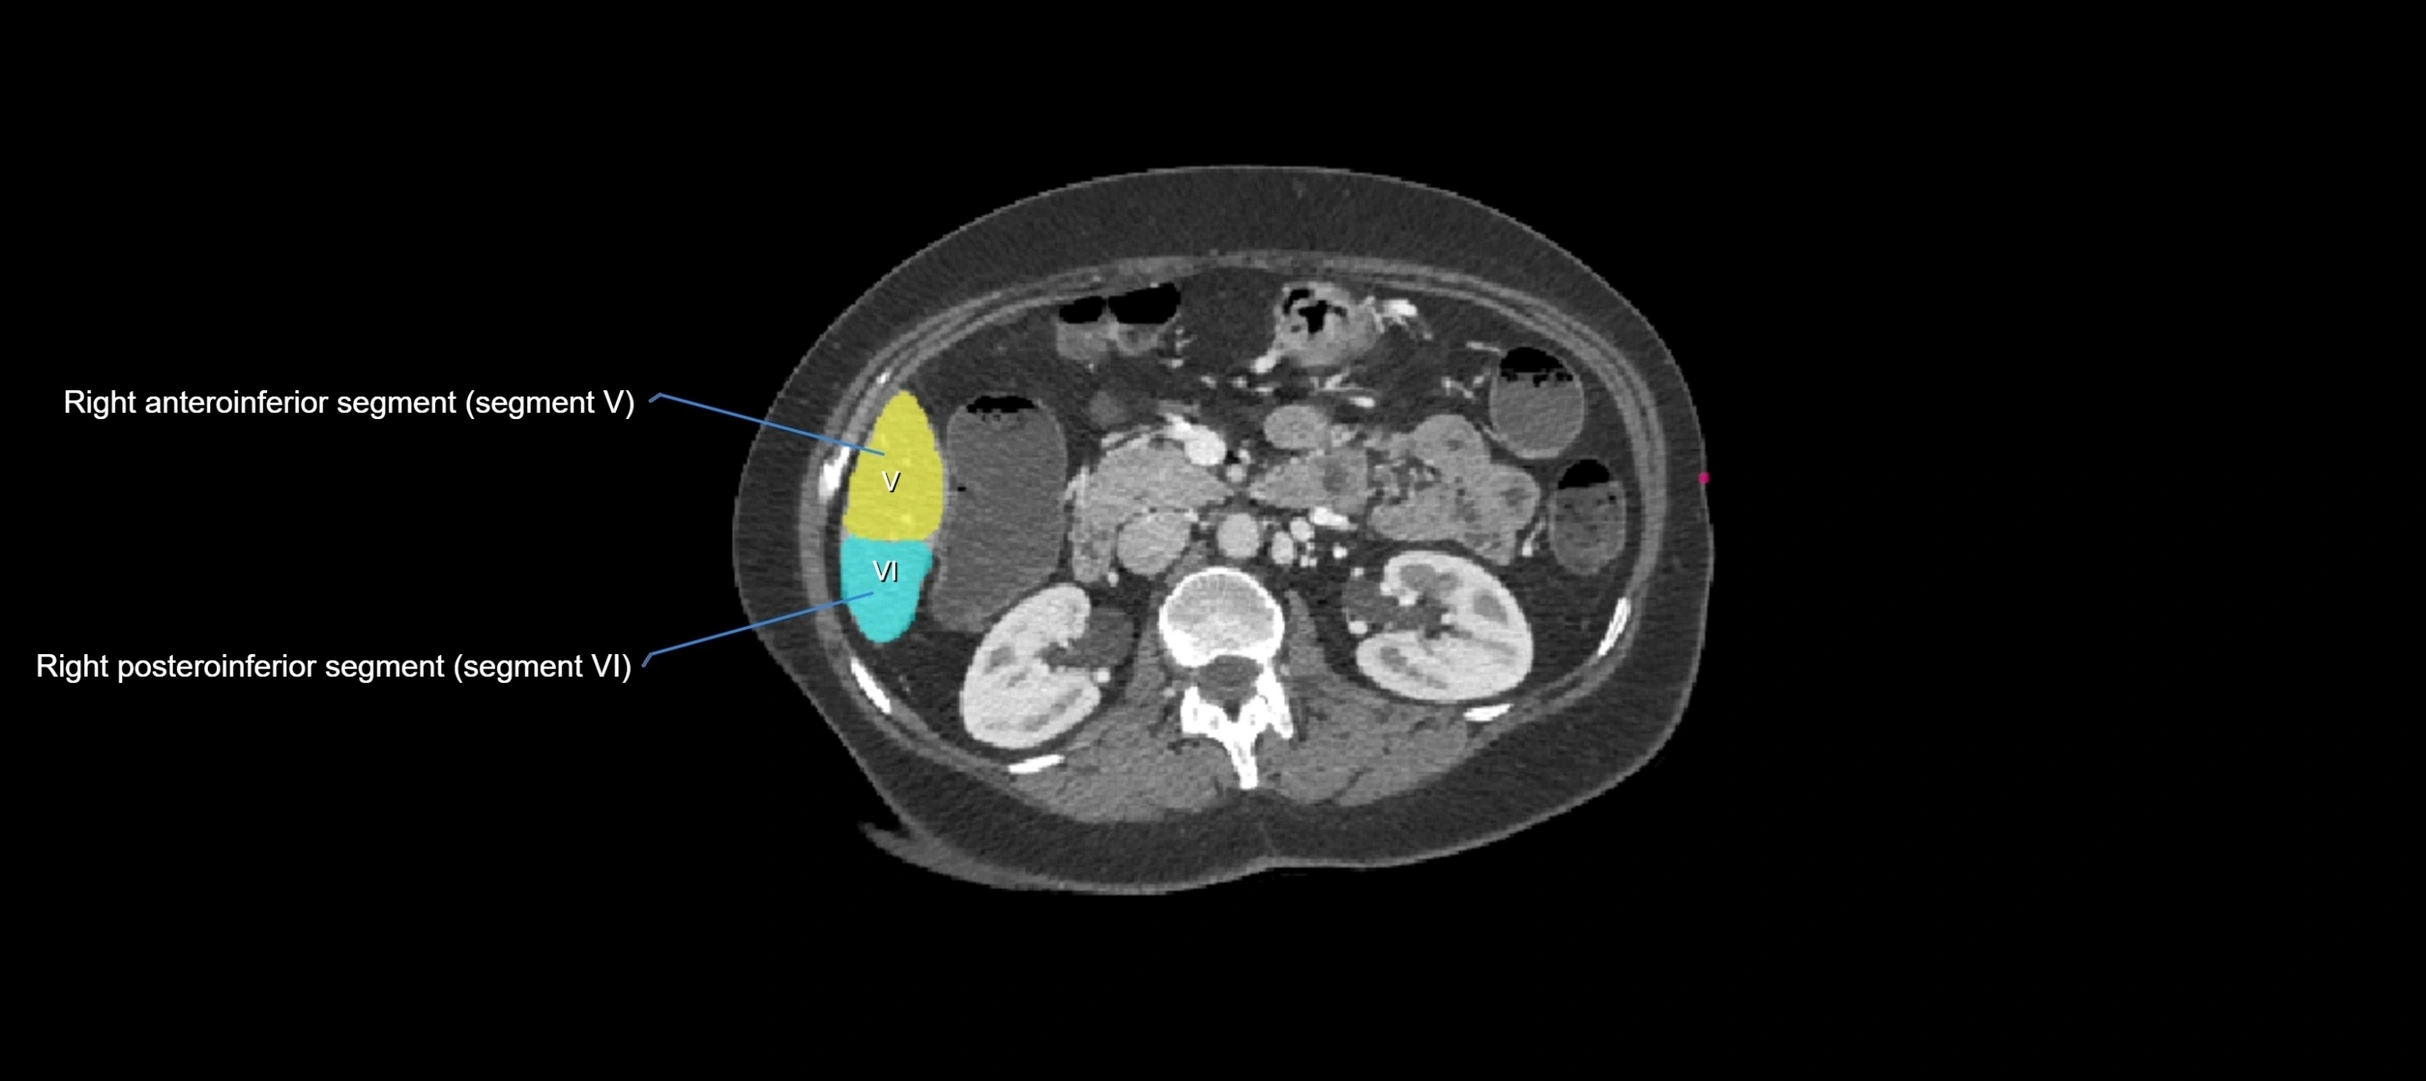

CT Image

image